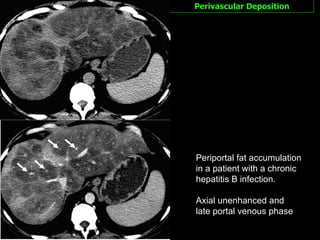

Perivascular Deposition This pattern is characterized by halos of fat that surround the hepatic veins, the portal veins, or both hepatic and portal veins.  The configuration is  tramlike  or tubular for vessels with a course in the imaging plane and  ringlike  or round for vessels with a course perpendicular to the imaging plane.

Perivascular Deposition An unequivocal signal  intensity loss on opposed-phase images  in comparison with that on in-phase images. The  lack of a mass effect  on the surrounded vessels are.  Indicative of the diagnosis The pathogenesis of perivascular fat deposition in the liver is unknown.

Perivascular Deposition Periportal fat accumulation in a patient with a chronic hepatitis B infection.  Axial unenhanced and late portal venous phase

Perivascular Deposition Periportalfat accumulation in a patient with a chronic hepatitis B infection. Axial unenhanced and late portal venous phase